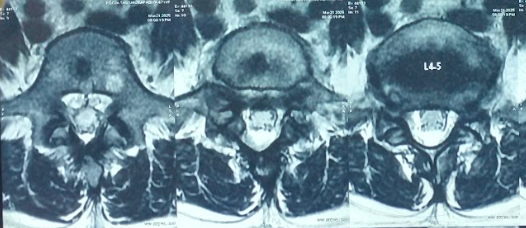

Diagnosis

- MRI – Best for early stress reactions and soft tissue assessment

- CT Scan – Gold standard for bony defect visualization